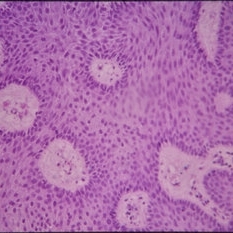

Histopathology of Linear Sebaceous Nevus Syndrome

Histopathology of Linear Sebaceous Nevus Syndrome

Feb 20 2015 by H. Michael Lambert, MD

Histopathology of linear sebaceous nevus syndrome.

Condition/keywords: histopathology, linear nevus sebaceous syndrome